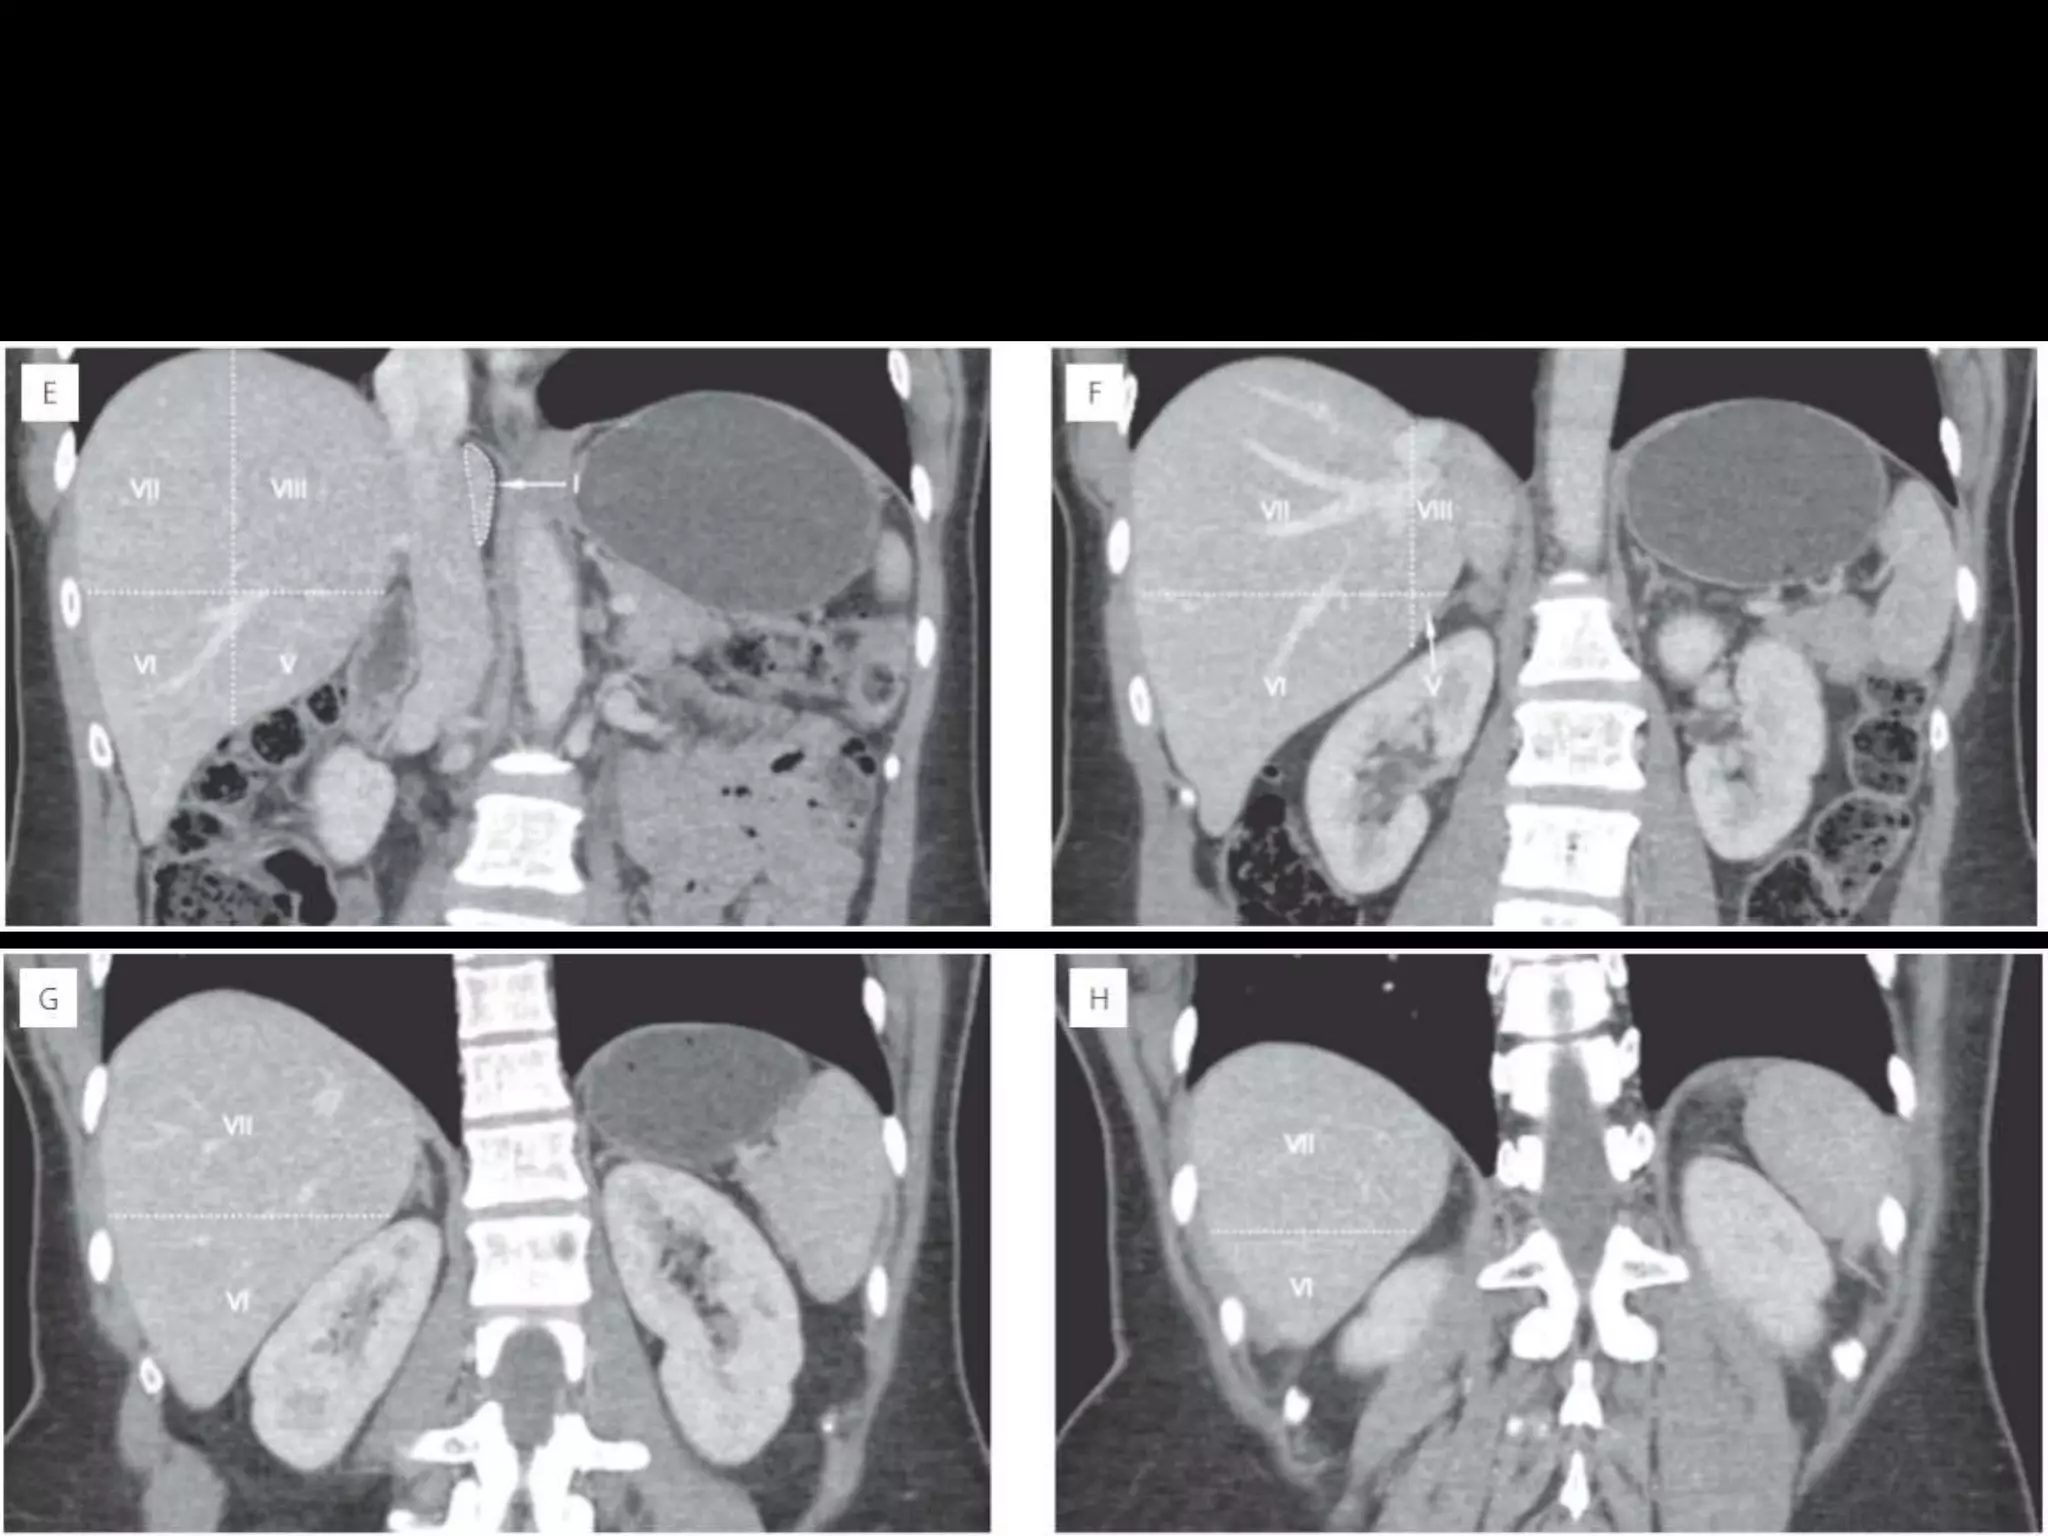

• 23.

How to separateliver segments on cross sectional imaging Left lobe: lateral(II/III) vs medial segment (IVA/B) Extrapolate a line along the falciform ligament superiorly to the confluence of the left and middle hepatic veins at the IVC (blue line). Left vs Right lobe: IVA/B vs V/VIII Extrapolate a line from the gallbladder fossa superiorly along the middle hepatic vein to the IVC (red line). Right lobe: anterior (V/VIII) vs posterior segment (VI/VII) Extrapolate a line along the right hepatic vein from the IVC inferiorly to the lateral liver margin (green line).